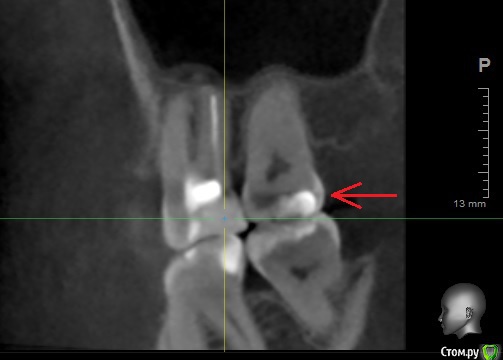

usilitel Опубликовано 17 ноября, 2018 Поделиться Опубликовано 17 ноября, 2018 (изменено) После замены пломбы в верхней 7-ке зуб окрасился и стал довольно сильно реагировать на холодное.Перед перепломбировкой 7-ки зуб иногда болел в области корней, после перепломбировки боли не прошли, плюс добавилась реакция на холодное. Вопросы: 1) Нормально ли, что зуб окрасился после перепломбировки?2) Может ли быть причина окраски в том, что зуб "отравлен" из-за токсичности пломбы в соседнем зубе? Снимок 1 ПОСЛЕ перепломбировки 7-ки: Снимок 2 ПОСЛЕ перепломбировки 7-ки: Рентгеновский снимок ДО перепломбировки 7-ки: Рентгеновский снимок ПОСЛЕ перепломбировки 7-ки - отсутствует. Моя версия (я не профессионал, так что сужу по собственным ощущениям):1,5 года назад при замене пломбы в соседней 6-ке пломбу скорее всего недосветили, и это сделало пломбу токсичной для зуба.1 год назад в 6-ке запломбировали каналы, но стало еще хуже (появилась невралгия, зуб реагирует при постукивании, зуд в области корней, болит глаз, стреляет в висок). При этом 6-ку удалять никто не хочет, т.к. на снимках всё более-менее нормально. Я думаю что из-за токсичности пломбы воспалились ткани вокруг 6-го зуба.Дальше это отравление в 6-ке перекинулось на 7-ку, и 7-ка тоже стала "отравленной". Из-за этого при замене пломбы 7-ка окрасилась и стала реагировать на холодное.Повторюсь - это моё непрофессиональное мнение, сужу по собственным ощущениям. Изменено 17 ноября, 2018 пользователем usilitel Ссылка на комментарий